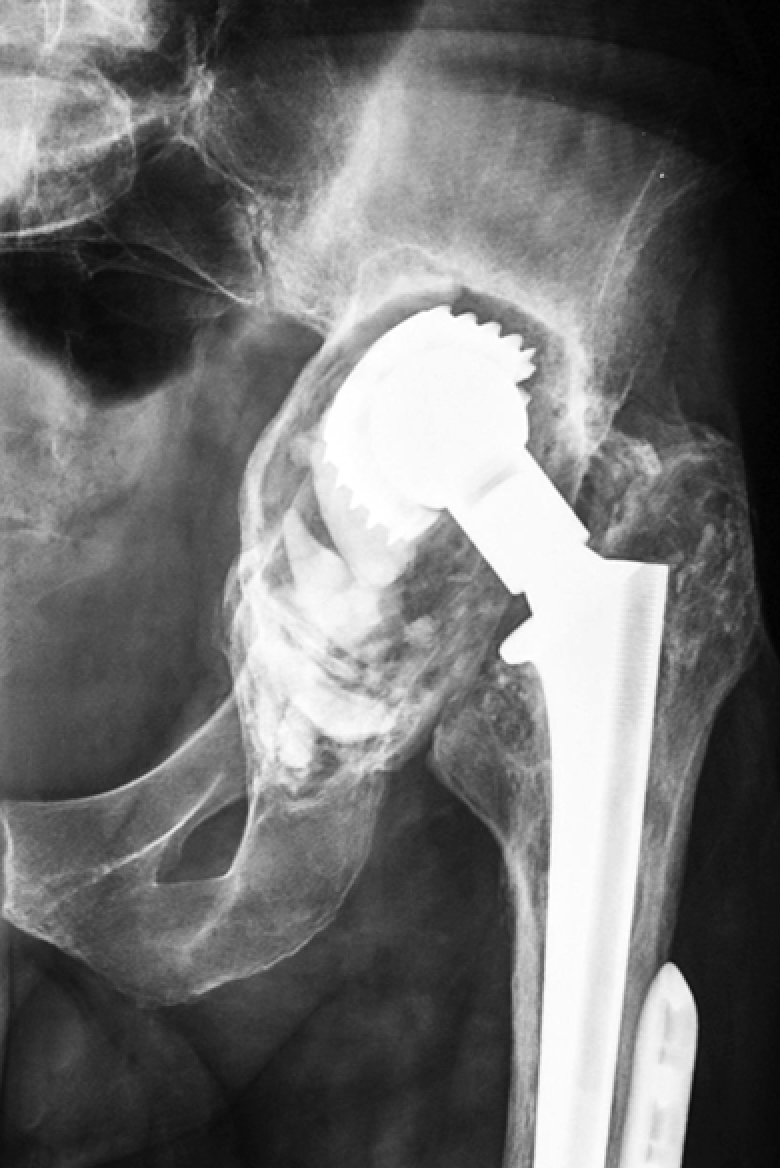

X-rays of patients with defects | ||||

Three-dimensional reconstructions of the pelvis of the same patients from the side of defect | ||||

Figure 2. Various options for acetabular reconstruction in Paprosky type 3B defect: a — lytic acetabular defect reconstructed using impaction bone grafting with implantation of a standard cemented acetabular component; b — complete anterior column defect reconstructed with an augment and a hemispherical acetabular component; c — complete medial wall defect reconstructed with augmentation and combined implantation of a hemicap cage; d — combination of complete medial wall and anterior column defects reconstructed with a Burch-Schneider antiprotrusio cage and a cemented acetabular component; e — combination of complete medial wall and posterior column defects reconstructed with a patient-specific acetabular component

Reconstruction of complete medial wall defects, as well as combined complete defects of the medial wall and anterior column, requires the use of antiprotrusio devices to ensure the stability of the acetabular component. For this combination of defects, a wide range of types and sizes of standard cages may be necessary (Figure 2 c, d). In cases of combined complete defects of the medial wall and posterior column — the most challenging in terms of biomechanical stability of the acetabular component — there is a need for a highly reliable primary fixation of the implant, which cannot always be achieved with standard revision systems (Figure 2 e).